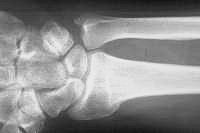

Preoperative radiographs demonstrate radial shortening and relative ulnar lengthening and ulnar carpal abutment.

Ulnar head prominence is obvious, associated with a fixed radial deviation of the wrist.